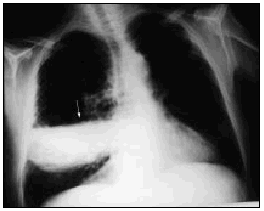

Varón de 60 años, diabético y con insuficiencia respiratoria crónica por enfisema pulmonar que ingresa por una neumonía en el lóbulo medio derecho. Se inició tratamiento con broncodilatadores inhalados, una cefalosporina de tercera generación y un macrólido, con mejoría inicial. En la tercera semana, ante la persistencia de cuadro febril, se realizó una radiografía de tórax (fig. 1) en la que se observa un infiltrado en el pulmón derecho de gran tamaño y con nivel hidroaéreo, por lo que se le añadió un antibiótico anaerobicida. En una TC torácica se observaba la lesión ya conocida (fig. 2. flecha izquierda) y otra pequeña imagen redondeada, con nivel hidroaéreo en su interior, en el espacio prevascular (fig. 2. flecha derecha). El fluido contenido en la lesión mayor era más denso que el agua y tenía burbujas de gas en su interior (fig. 2 punta de flecha). En un cultivo de esputo se cultivó Pseudomonas aeruginosa multisensible. Tras un acceso de tos, en una nueva radiografía de tórax (fig. 3) desaparece el infiltrado derecho, diseminándose la infección pulmonar, falleciendo el paciente días después en situación de shock séptico. Se estableció el siguiente diagnóstico: bullas pulmonares infectadas; bronconeumonía bilateral por P. aeruginosa.

Fig. 3.